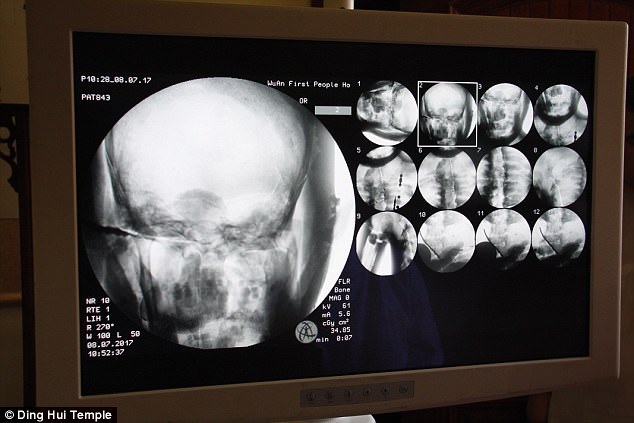

Ngày 8/7/2017, trước sự chứng kiến của các nhà sư, giới truyền thông và nhiều người dân, các nhà khoa học đã tiến hành chụp CT xác ướp nhà sư Ci Xian.

Ban quản lý của ngôi chùa đã sắp xếp một buổi chụp CT xác ướp nhà sư Ci Xian vào ngày 8 tháng 7 năm 2017.

Mọi người đều bàng hoàng khi các bác sĩ cho biết nhà sư Ci Xian vẫn còn nguyên bộ xương, và một bộ não hoàn chỉnh. Tức xác ướp này đã được bảo quản gần như nguyên vẹn sau hơn 1.000 năm. Điều này khiến giới khoa học sửng sốt với kỹ thuật ướp xác thời bấy giờ.

Bác sĩ Wu Yongqing nói với kênh Pear Video sau khi tiến hành chụp CT cho xác ướp: "Chúng tôi có thể thấy xương của ngài ấy khỏe mạnh như một người bình thường. Hàm trên, răng trên, xương sườn, xương sống và tất cả các khớp đều vẫn nguyên vẹn. Thật không thể tin được khi thấy điều này".